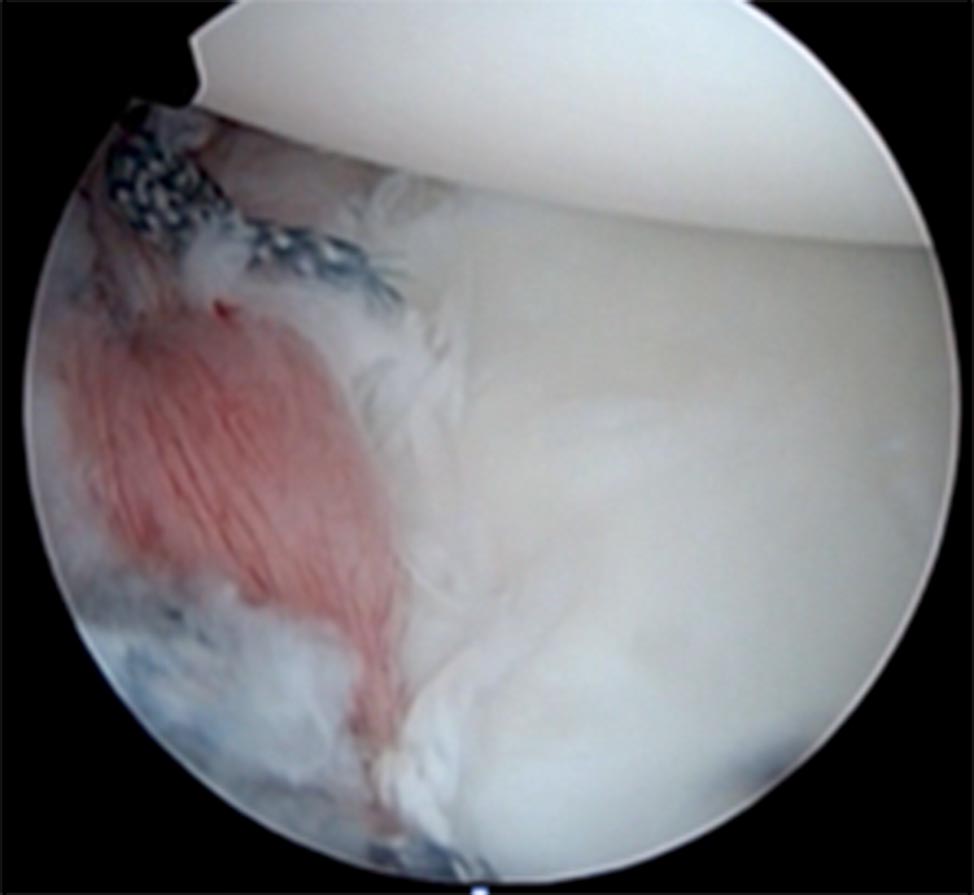

Se realiza decolamiento del labrum para su movilización con liberador de tejido y el cruentado del cuello de glena. Se realiza el cruentado del margen condral con cureta circular y shaver. Se colocaron 2 anclas reabsorbibles doble sutura en reborde glenoideo posterior, hora 7 y hora 8 (fig. 3). Se realiza plicatura capsular posterior y reinserción del labrum posterior, con las cuatro suturas.